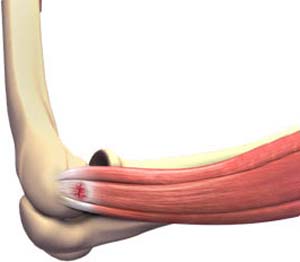

Tennis Elbow

Tennis elbow is the common name used for the elbow condition called lateral epicondylitis.

Tennis elbow, also called lateral epicondylitis, is a painful condition occurring from repeated muscle contractions in the forearm that leads to inflammation and micro-tears in the tendons that attach to the lateral epicondyle.